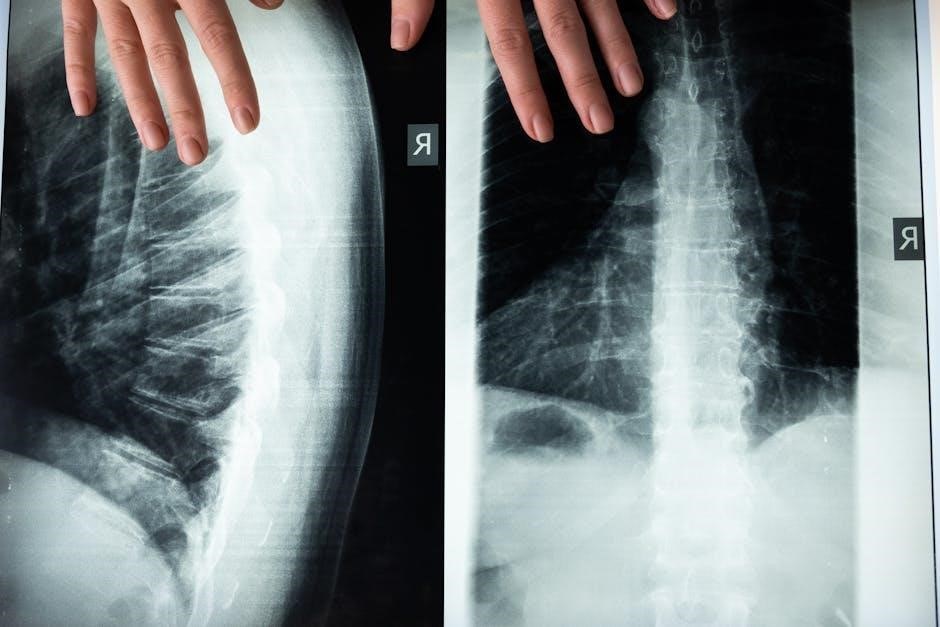

While PDF guides offer TOS exercises, imaging and nerve conduction studies are vital for accurate diagnosis, informing exercise program design. X-rays can reveal bony abnormalities, while MRI or CT scans visualize soft tissues, identifying structural causes of compression.